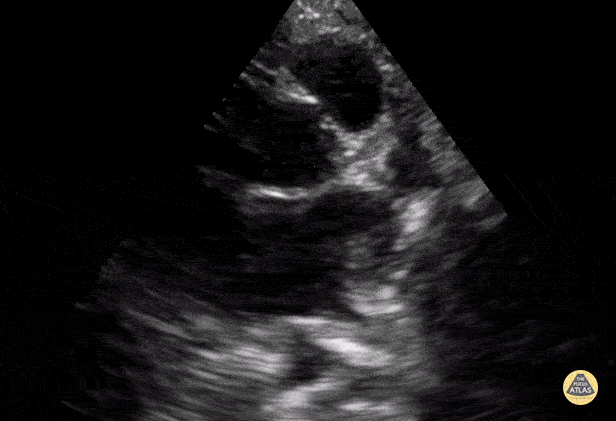

Normal PSSA base (aorta) view in a 9-year-old. Contributor: Jaron Smith, MD, Phoenix Children's Hospital